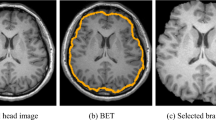

We propose a new method for hearing loss classification from magnetic resonance image (MRI), which can automatically detect tissue-specific features in a given MRI. Sensorineural hearing loss (SHNL) is highly prevalent in our society. Early diagnosis and intervention have a profound impact on patient outcomes. A solution to provide early diagnosis is the use of automated diagnostic systems. In this study, we propose a novel Deep-HLNet framework, based on few-shot learning, for the automated classification of SNHL. This research involves magnetic resonance (MRI) images from 60 participants of three balanced categories: left-sided SNHL, right-sided SNHL, and healthy controls. A convolutional neural network was employed for feature extraction from individual categories, while a neural network and a comparison classifier strategy constituted a tri-classifier for SNHL classification. In terms of experiment results and practicability of the algorithm, the classification performance was significantly better than the standard deep learning methods or other conventional methods, with an overall accuracy of 96.62%.